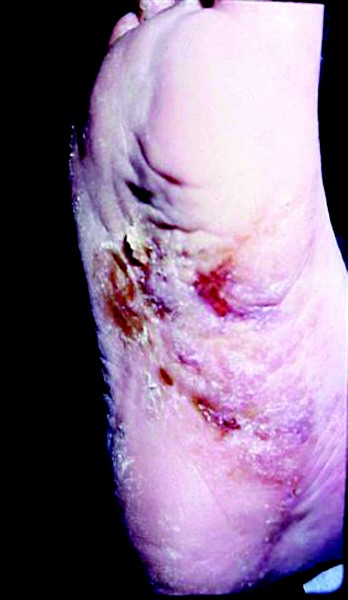

The Linden studies demonstrate that ciclopirox functionally activates HIF-1 and induces VEGF transcription as well as angiogenesis. The authors observed that wound healing in the skin may be complicated by microbial invasion, inflammation and ischemia, leading to ulceration. As ciclopirox is lipophilic, antimicrobiotic, antiinflammatory, angiogenic and does not affect healthy tissue, it might be beneficial for the topical treatment of skin wound tissue.4 The implications of potential wound-healing properties in the antifungal ciclopirox are especially noteworthy for podiatrists who are all too familiar with the various simple and complex infections that can lead to chronic wounds (see “Understanding The Connection Between Common Infections And Chronic Wounds” below). These infections result from a combination of factors including disease, injury, neuropathy, vascular impairment and inefficient wound healing. Severe complications leading to wounds in the feet and lower leg occur as a result of chronic infections, pathogenic resistance to drugs and lack of treatment.21,22

The incidence of severe and chronic wounds among patients with diabetes has risen dramatically in the United States. Type 1 and 2 diabetes afflict an estimated 17 million people and up to 15 percent of those patients will undergo lower-extremity amputation.23,24 Public health officials estimate 800,000 new cases of diabetes are diagnosed annually. Diabetes patients will undergo lower-extremity amputations at an increasing rate, with approximately 80 percent of those amputations primarily caused by chronic foot ulcers.23-25 Similar to patients with diabetes, those with peripheral vascular disease and those who are immunocompromised frequently suffer lower extremity complications because of fungal and bacterial infections. Three of the most common clinical presentations podiatrists see are tinea pedis, onychomycosis and paronychia. Dermatophytes are commonly the underlying basis for tinea pedis and other fungal and bacterial infections.26 Although nail infections are preceded by a dermatophyte, the symptomatic patient may have a more complex infection, complicated by pyogenic bacteria or other fungal species.27 Currently, ciclopirox is indicated for topical treatment of a broad range of dermal fungal infections including: tinea pedis, tinea cruris and tinea corporis due to Trichophyton rubrum, T. mentagrophytes, Epidermophyton floccosum and Microsporum canis; candidiasis due to Candida albicans; and tinea versicolor due to Malassezia furfur.1,28 Ciclopirox also has in vitro activity against many Gram-positive and Gram-negative bacteria including Escherichia coli, Proteus mirabilis, Pseudomonas aeruginosa, and Staphylococcus and Streptococcus species.2 There is also evidence that ciclopirox may exhibit better antiinflammatory activity than 2.5% hydrocortisone.3